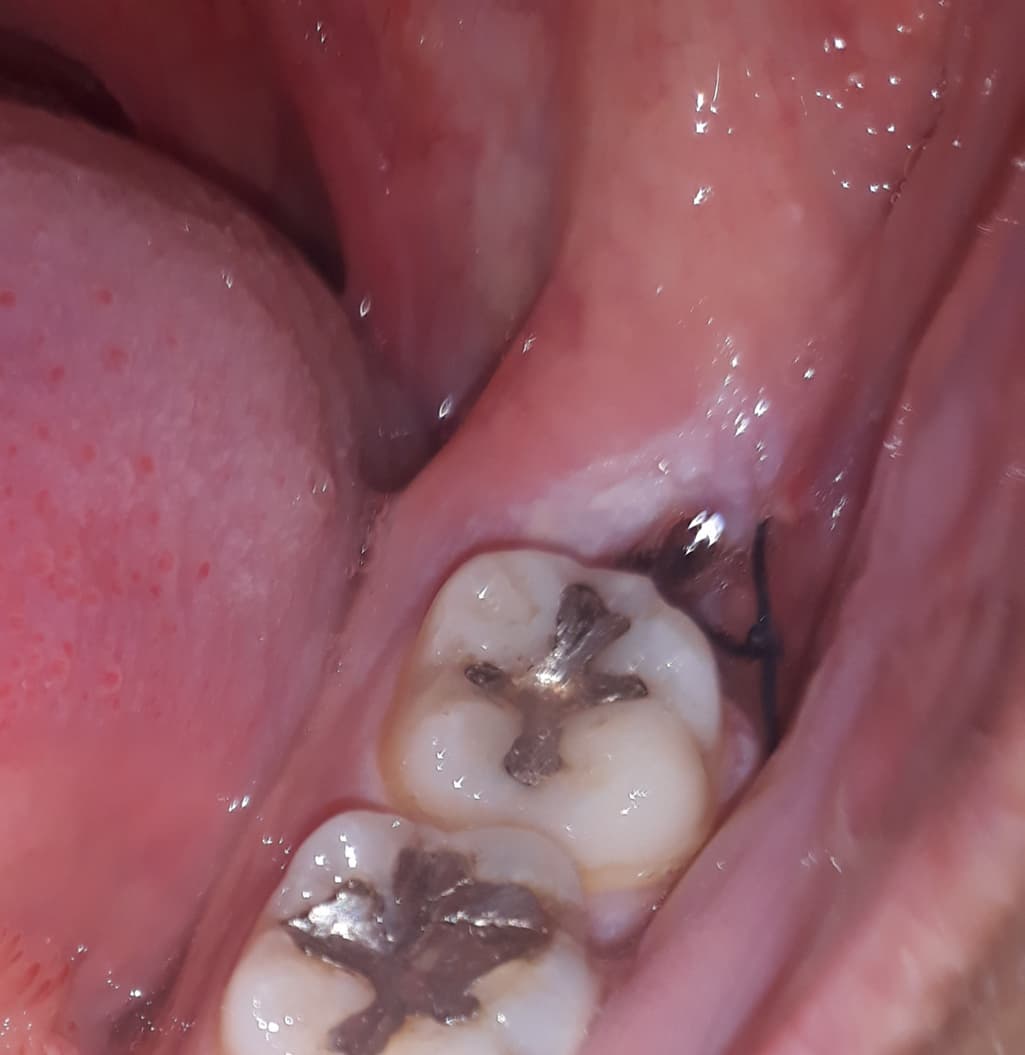

사랑니 발치하고 난 후 이게 피떡이 점점 사라져요

발치하고 최대한 오래 물고 있으라고 해서

4시간동안 묵언수행한다음에 빼서 빨간 피떡같은게 꽉 차있었는데

날이 갈수록 점점 사라져요

사랑니를 발치한 후 지혈을 하고 생긴 피떡이 계속 유지될 필요는 없습니다. 자연스럽게 소실되어야 하며 올리신 사진으로 정확한 상태를 알 수 없지만 크게 문제될 것은 없어 보입니다.

피떡의 경우 자연스럽게 제거가 되어가는 과정이며, 점차 안에서 살이 차오르면서 빈 공간은 매워질 수 있습니다. 통증지속시 치과에 재내원하여 주시고, 그동안 가글을 꾸준히 하시어 염증방지를 하시는 것이 좋겠습니다.